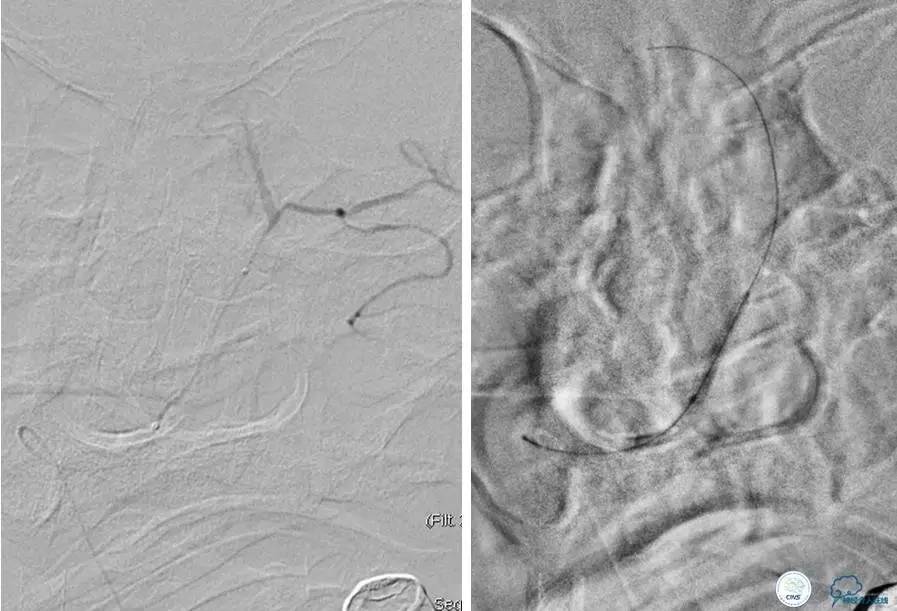

患者:53岁男性,反复脑梗死3个月。

▼给予球囊扩张成形,闭塞段较长,决定药物治疗视察,二期再给予支架治疗。

▼药物治疗1个月,再次发作。再次来我院支架治疗。

▼支架术后,效果好。

因此,某些患者分期治疗也具有合理性。